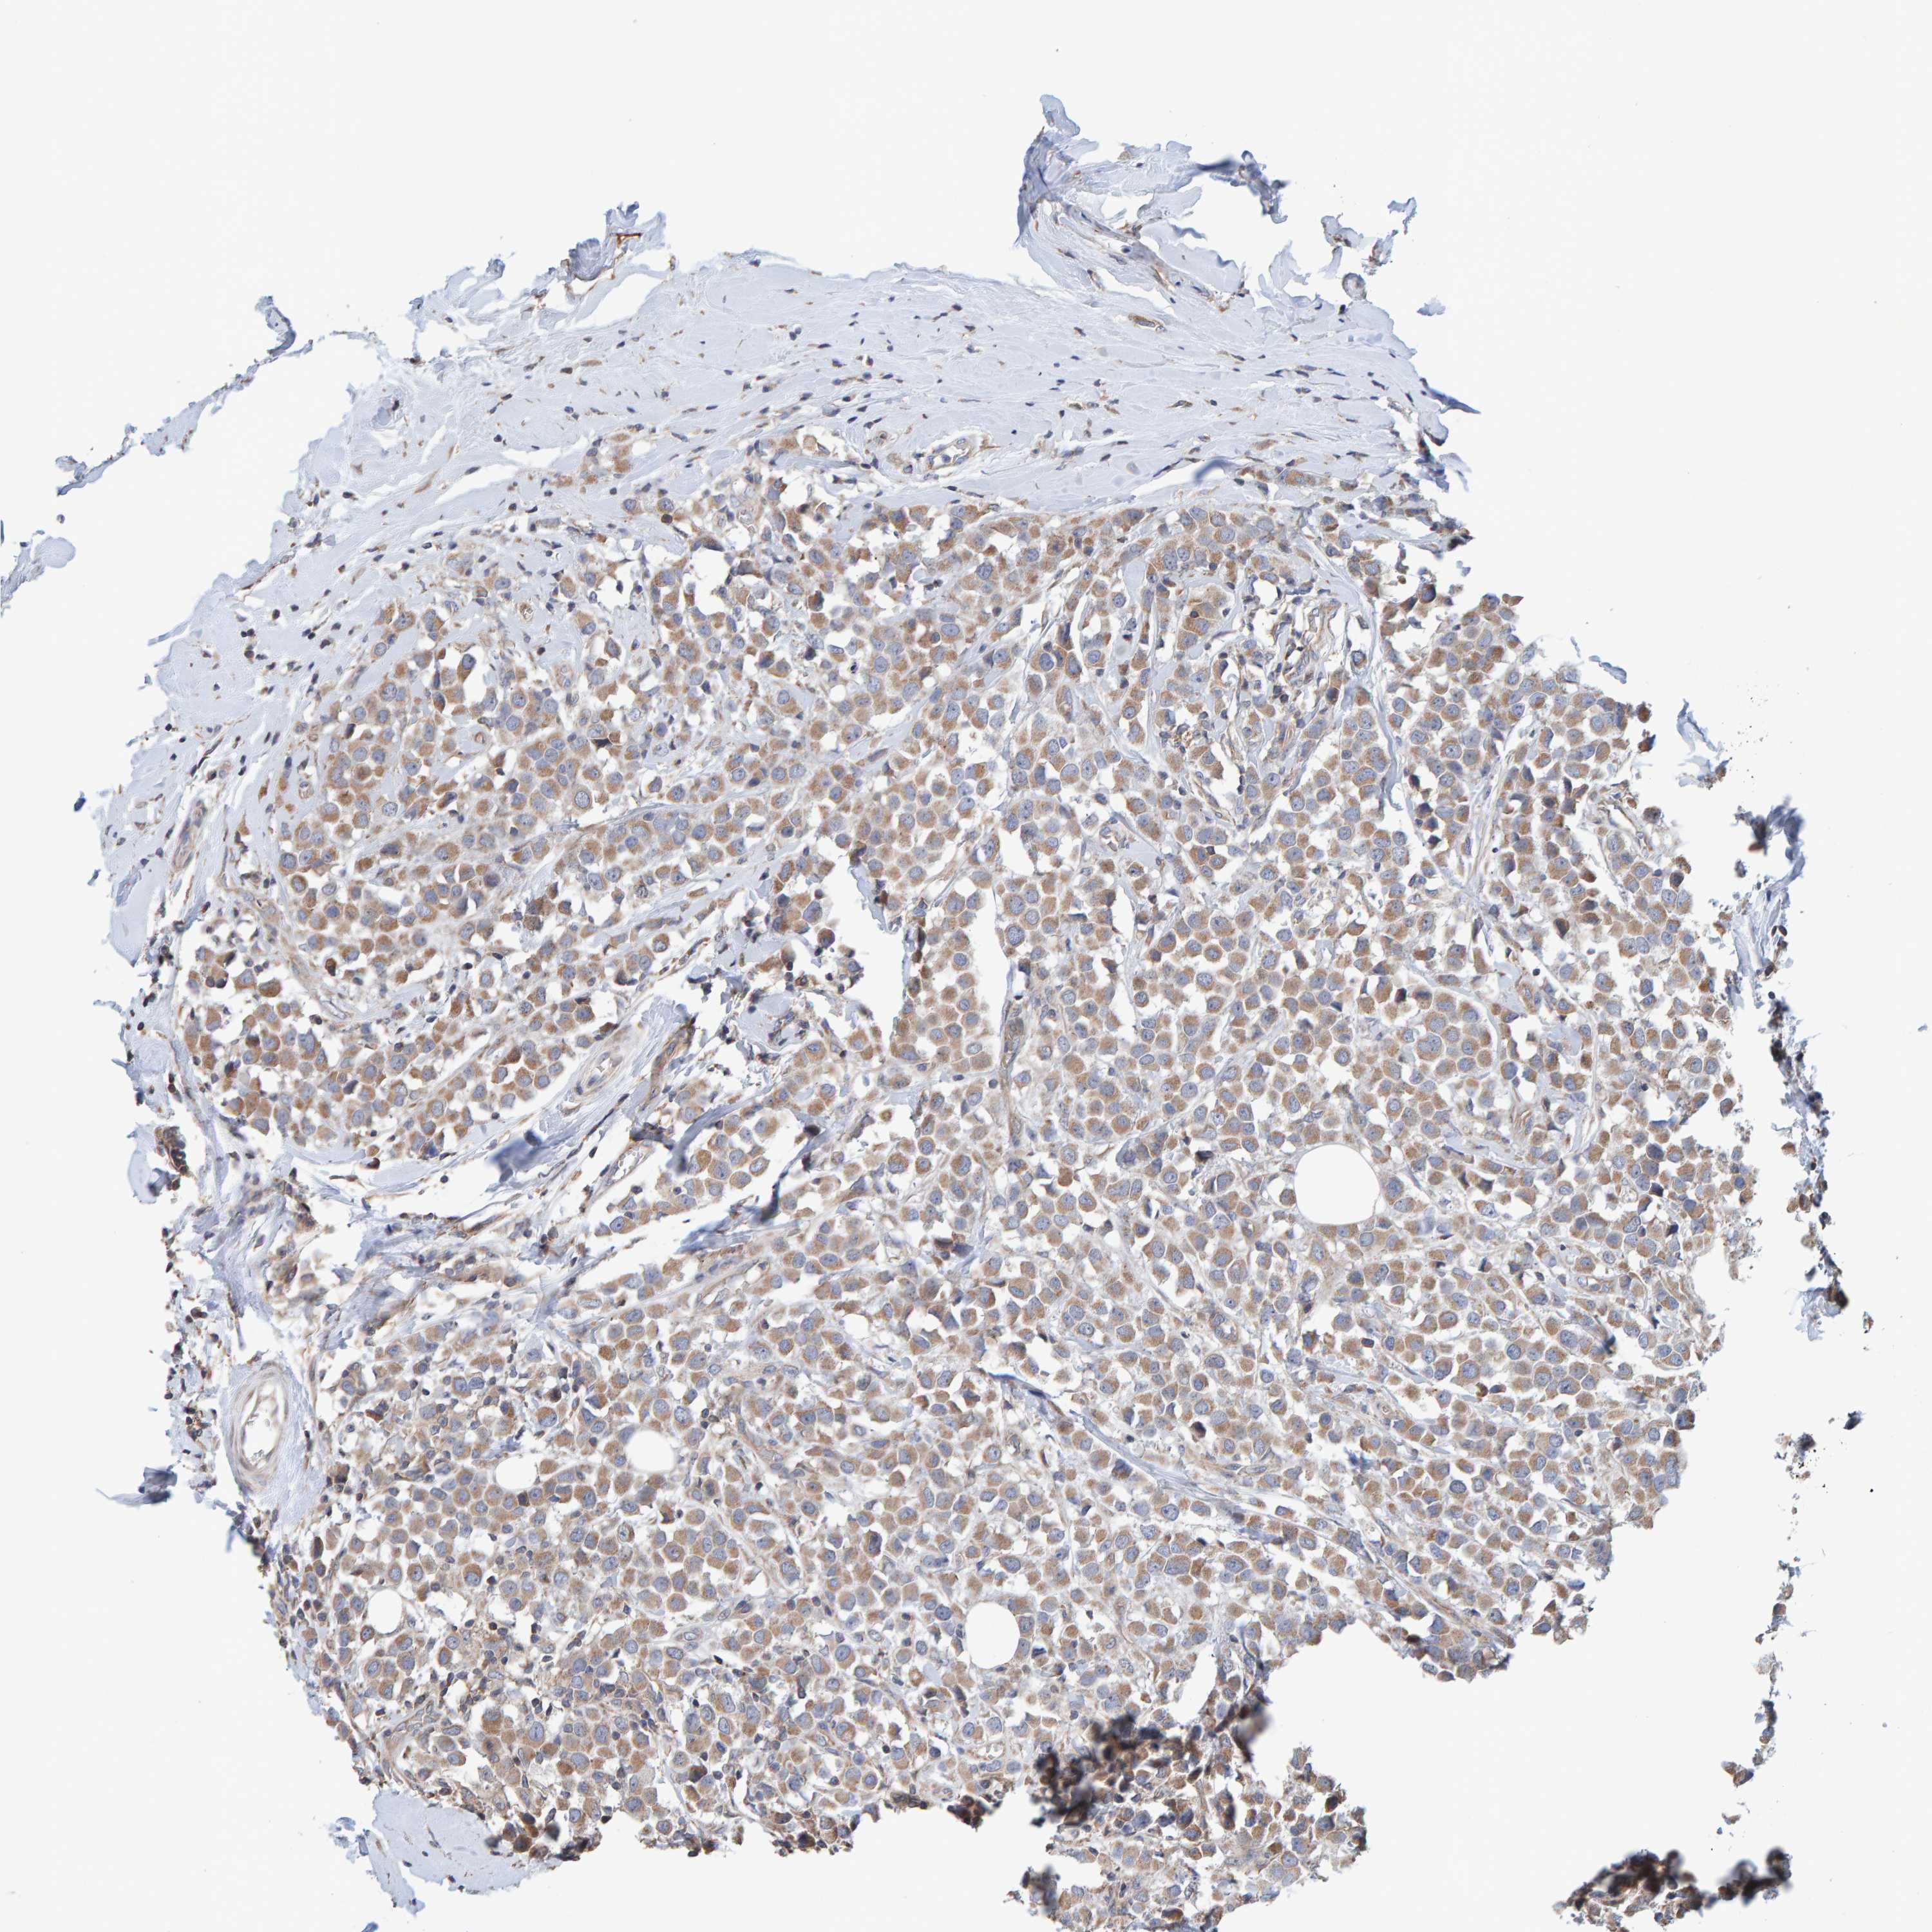

BRCA TCGA BRCA VALIDATION PROTEIN EXPRESSION

ANTIBODIES

AND

VALIDATION